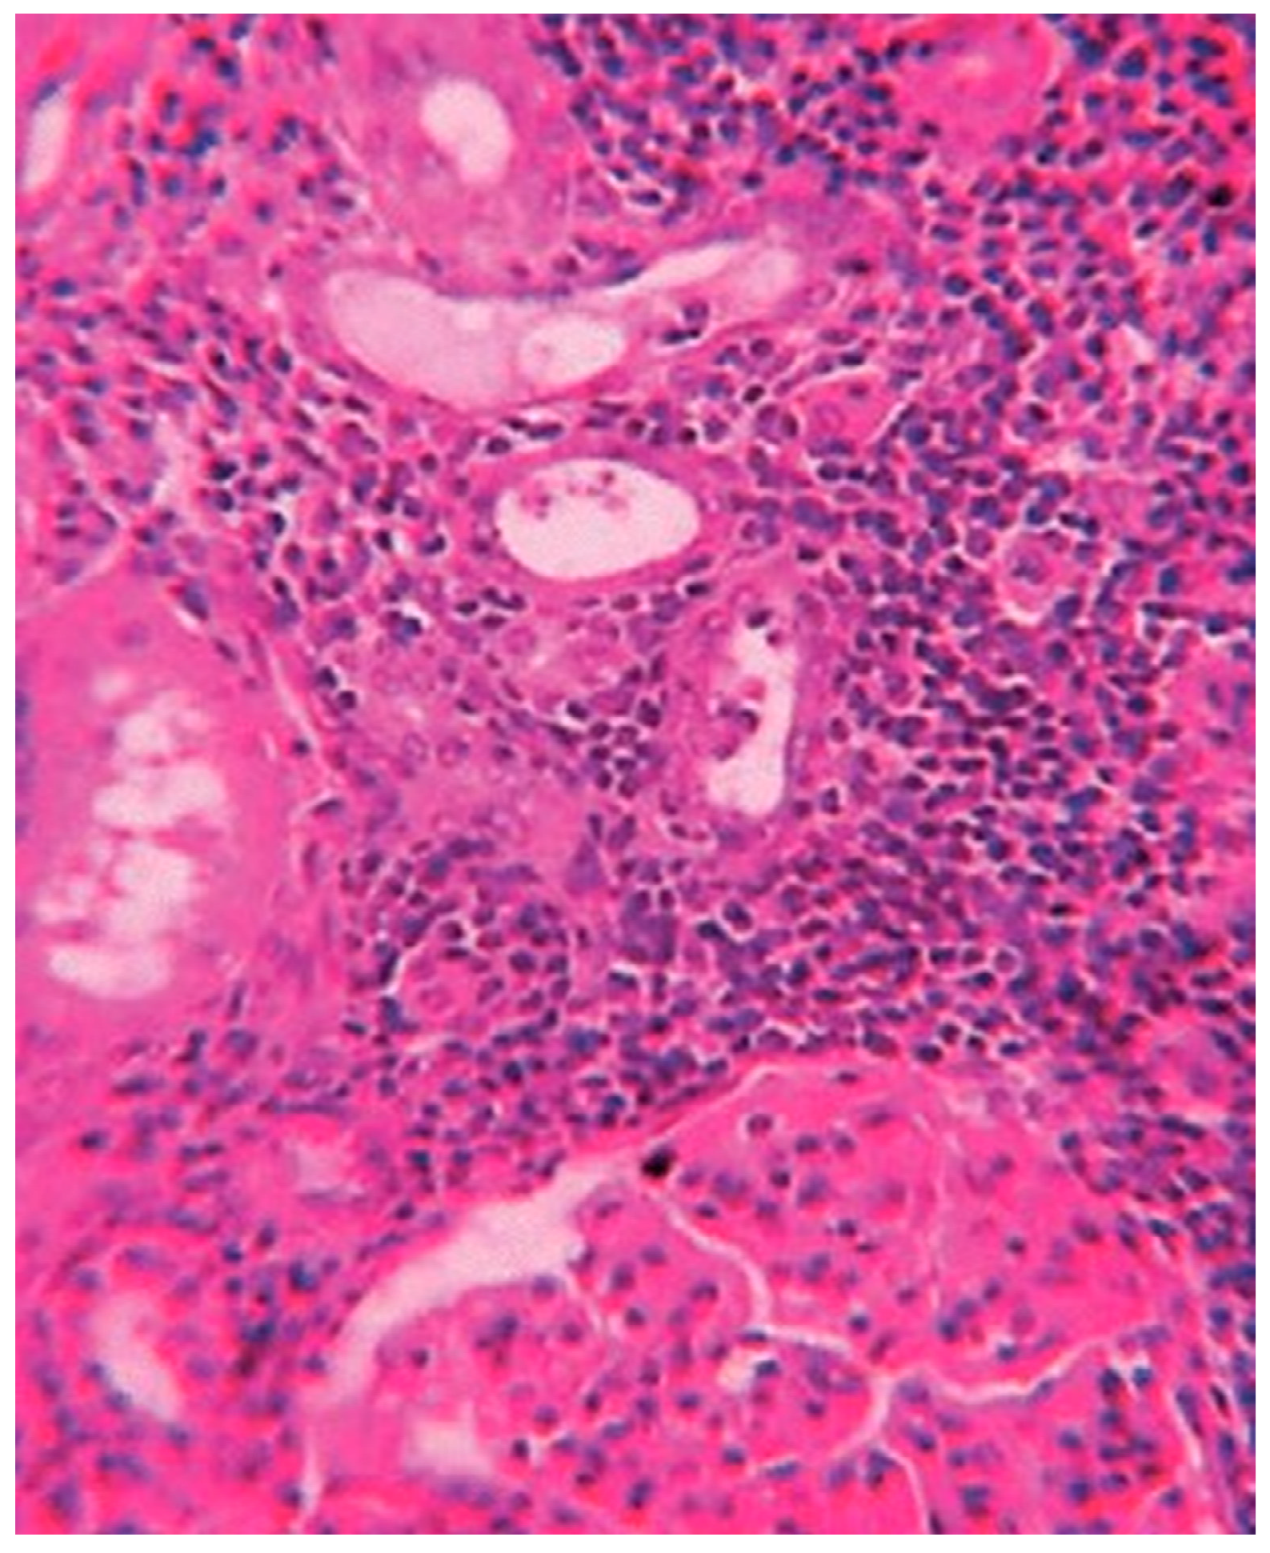

Histological exams showed a degenerative myocardiopathy and segmental vascular insufficiency, associated with myocardial micronecrosis foci. Lungs presented diffuse alveolar damage, with chronic interstitial pulmonary disease. Kidney showed necrotic degenerative changes of the tubules and glomeruli with interstitial nephritis (see Figure 2). The presence of the greenish liquid was confirmed in the stomach and in the small intestine, with both presenting mucosal inflammation and gastric necrotic areas (see Figure 3). Finally, there was mild fatty liver disease.

Figure 2. Tubular degeneration and necrosis of the kidney.